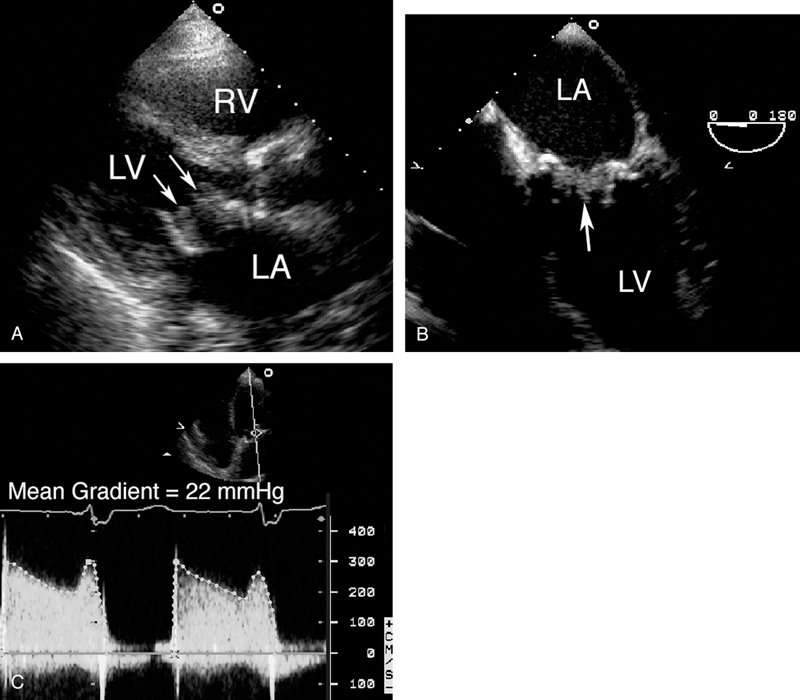

فحوصات تشخيصية لبعض امراض القلب والشرايين التاجية